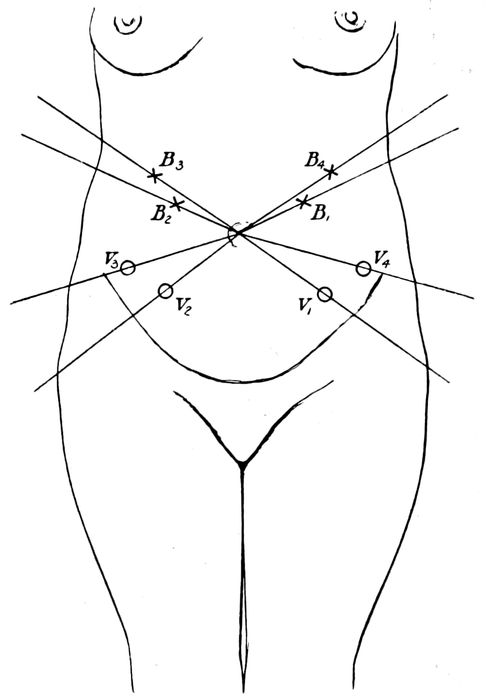

Points of greatest intensity of fœtal heart tones |

| |